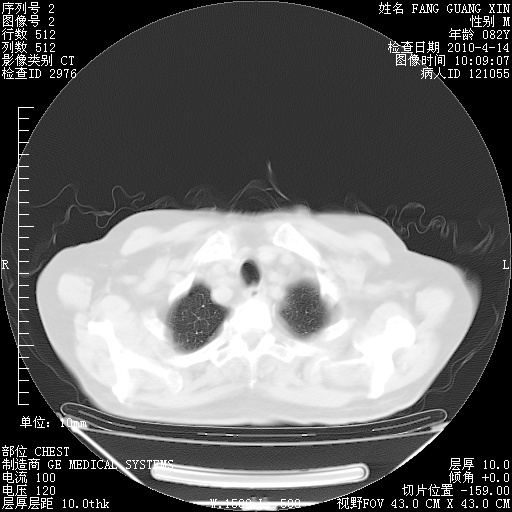

4月28日肺部CT——再次出现类似去年5月9日——透光度降低,(影像科认为)“间质性”改变。

4月28日肺部CT——再次出现类似去年5月9日——透光度降低,“间质性”改变。